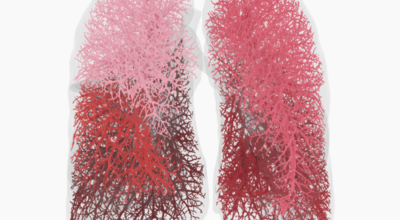

3. 폐렴 증상 - 호흡 곤란

초기에 가벼운 기침으로 시작해 호흡하는 것조차 힘들어지게 되는데요 폐에 발생한 염증으로 인해서 폐의 신전성이 감소하고, 폐를 구성하는 폐포 세포가 망가져 적정 수준의 산소를 보관하지 못하기 때문에 호흡곤란이 유발될 수 있어요.